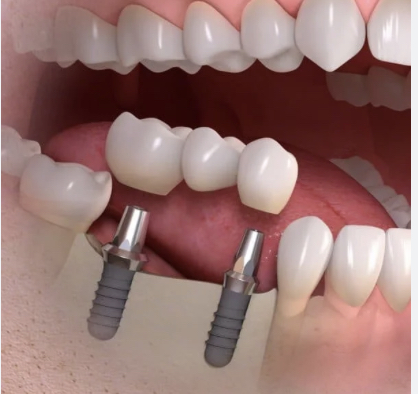

Prosthetics and Implantology

The recovery of one or several dental pieces or complete sectors is done with fixed or removable prosthesis. An individualized study is necessary to decide the best option for each loss.